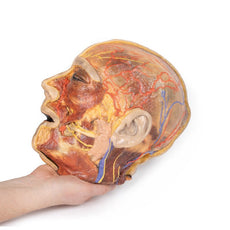

3D Printed Sagittal Section of Head with Infratemporal Fossa Dissection

3D Printed Sagittal Section of Head with Infratemporal Fossa Dissection

This 3D model provides a combined midsagittal section through the head and

superior neck coupled with a deep dissection into the infratemporal fossa

region and superficial dissection of the scalp.

On the opposing side of the model, a superficial and deep dissection has

opened a large window into the anatomy of the lateral scalp and infratemporal

fossa. Across the scalp there is a well preserved posterior auricular nerve

and superficial temporal artery highlighted on the superficial surface of the

temporalis muscle. Anteriorly, the temporalis has been dissected to expose

the deep temporal arteries arising from across the maxillary artery.